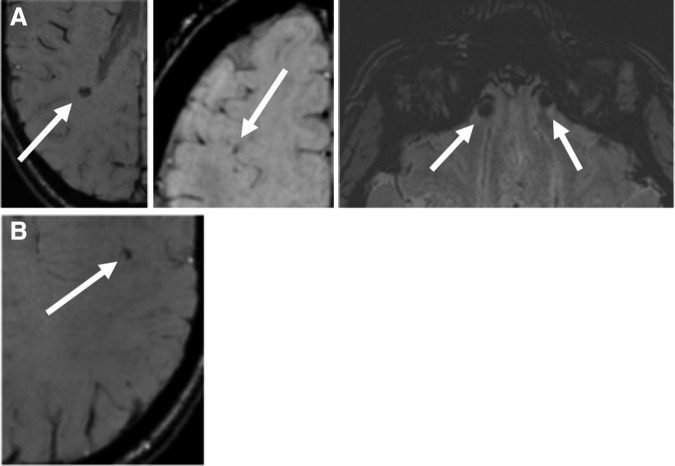

Susceptibility weighted imaging

Possible micro-hemorrhages were found in one participant in the NA group in the right temporal, bilateral inferior frontal, and right frontal lobes (Fig. 1A), and one participant in the A-NCS group in the left frontal lobe (Fig. 1B). A Kruskal-Wallis H test showed no difference between the three groups (h = 1.01, p = 0.60).

FIG. 1.

Possible micro-hemorrhages in participants. (A) Nonathlete (right temporal, bilateralinferior frontal, and right frontal lobes). (B) Athlete in a noncontact sport (left frontal lobe).